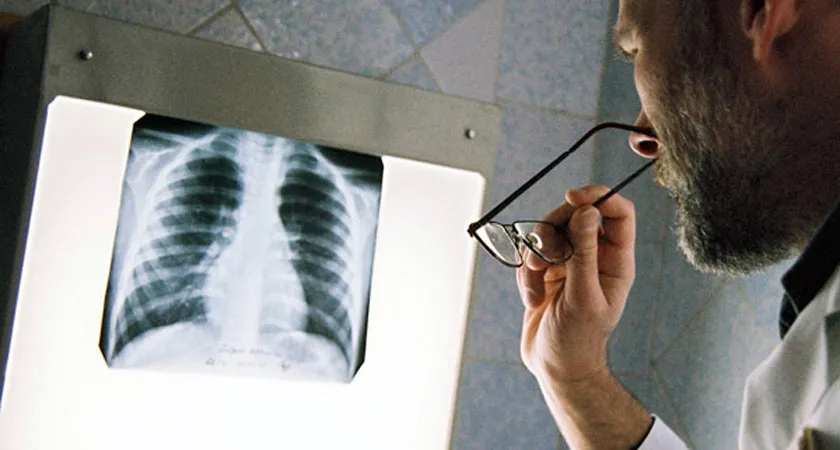

Как сообщает пресс-служба кабинета министров, Постановление от 6 августа 2014 года №773 устанавливает, что в рамках программ реализуются мероприятия по укреплению материально-технической базы государственных и муниципальных организаций здравоохранения, текущий и капитальный ремонт объектов медицинских организаций, приобретение и монтаж медицинского оборудования, включая приобретение санитарного транспорта, а также по внедрению современных информационных систем.